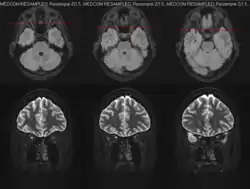

MRI

Magnetic resonance imaging (MRI) is a robust and sensitive diagnostic modality for the detection of optic neuritis. Imaging of the optic nerve with MRI shows increased signal on the affected side. There is contrast enhancement of the symptomatic optic nerve and sheaths acutely or intrinsic signal increase (looking brighter) within ≥ 3 months. One study found that MRI of the orbits with fat suppression and gadolinium enhancement detected acute optic neuritis lesions in 95% of affected individuals within 20 days of vision loss.[23] Another study found that T2-weighted images with fat suppression and short tau inversion recovery (STIR) detected lesions in up to 89% of acute optic neuritis cases with abnormalities persisting for as long as 6 weeks in 92% of cases.[24]

Identification of optic nerve, orbital, brain, and meningeal involvement with MRI can also help to better characterize the underlying cause of optic neuritis upon initial evaluation. Unilateral optic nerve involvement is more common MS while bilateral optic nerve involvement is more common in NMOSD and MOGAD.[7] T2-hyperintense and gadolinium-enhancing lesions in multiple regions of the brain and/or spinal cord may be highly suggestive or diagnostic of MS. Such lesions found in the periependymal, fornix, and hypothalamic lesions may be more suggestive of NMOSD.[7] Involvement of the optic chiasm or optic tract are more suggestive of NMOSD-optic neuritis; involvement of the retrobulbar optic nerve can be seen in both NMOSD and MOGAD, but more commonly in MOGAD; perineural optic nerve involvement is often suggestive of MOGAD-optic neuritis, but should not preclude the investigation of other autoimmune or infectious etiologies.[7]